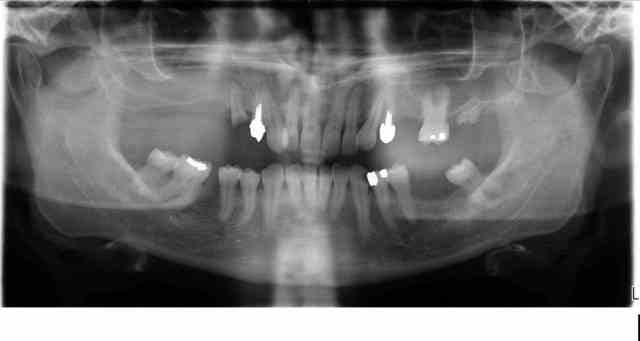

Voila la pano.

Le cas est difficile car le patient presente une edantation sup et inferieur prononcée. Une prise d'empreinte sectorielle dans ce cas peut elle prendre en compte les parametres suffisants pour la pose de protheses ainsi que les infos necessaires a leur realisation? Quelles sont vos idées

la pano